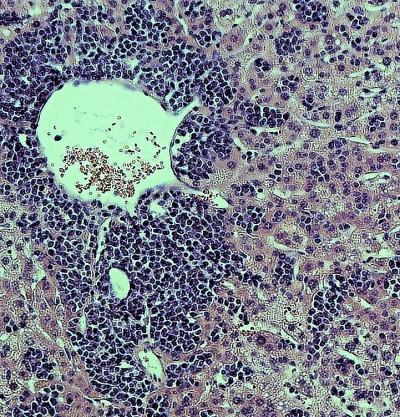

To explore how viruses interact with their hosts, and how these processes lead to virulence and disease, Alexander Ploss, assistant professor of molecular biology, and colleagues at Princeton University adapted a technique -- called RNA Prime flow -- that can detect RNA molecules within individual cells. They used the technique to track the presence of replicating viral particles in various immune cells circulating in the blood of infected mice. Mice are usually resistant to YFV, but Ploss and colleagues found that even the attenuated YFV-17D strain was lethal if the transcription factor STAT1, part of the antiviral interferon signaling pathway, was removed from mouse immune cells. The finding suggests that interferon signaling within immune cells protects mice from YFV, and that species-specific differences in this pathway allow the virus to replicate in humans and certain other primates but not mice.

Accordingly, YFV-17D was able to replicate efficiently in mice whose immune systems had been replaced with human immune cells capable of activating interferon signaling. However, just like humans immunized with the attenuated YFV vaccine, these "humanized" mice didn't develop disease symptoms when infected with YFV-17D, allowing Ploss and colleagues to study how the attenuated virus interacts with the human immune system. Using their viral RNA flow technique, the researchers determined that the virus can replicate inside certain human immune cell types, including B lymphocytes and natural killer cells, in which the virus has not been detected previously. The researchers found that the panel of human cell types targeted by the virus changes over the course of infection in both the blood and the spleen of the animals, highlighting the distinct dynamics of YFV-17D replication in the human immune system.